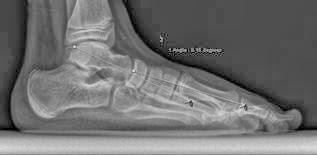

Finalmente abajo os muestro las radiografías antes y después de la operación. Se muestra lo que se llama el ángulo astrágalo-metatarsiano (línea de Meary) corregido con la cirugía, que es lo que la intervención rectifica para revertir el pie plano: